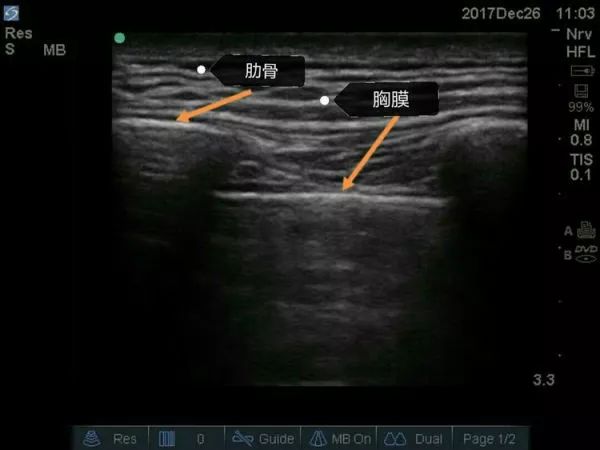

超声下肋骨及胸膜